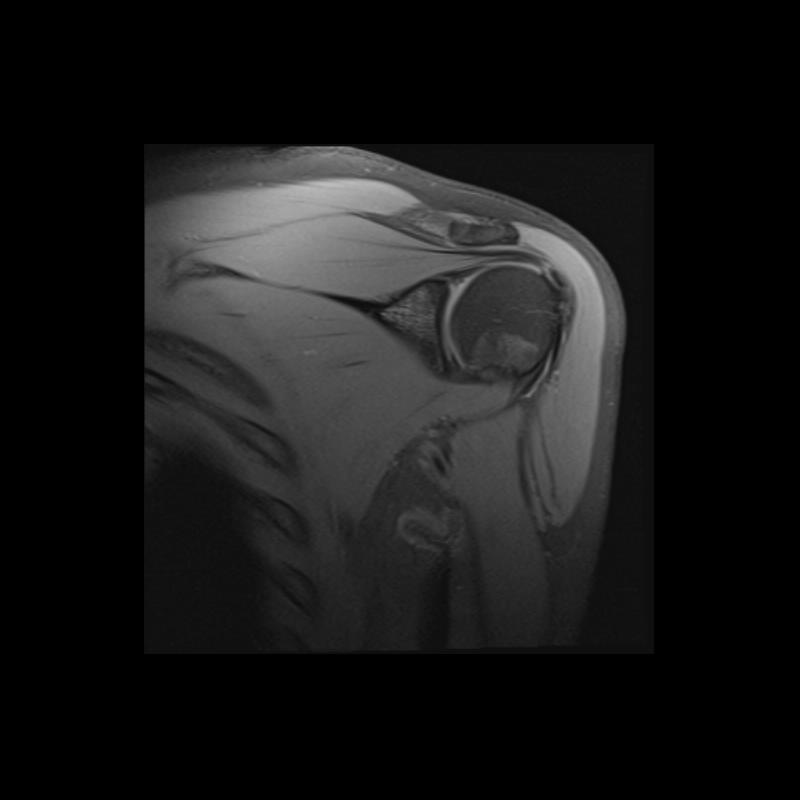

Shoulder MRI Anatomy